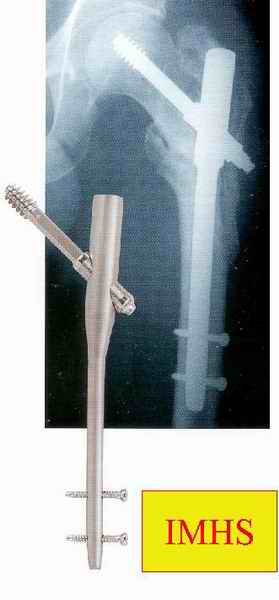

IMHS